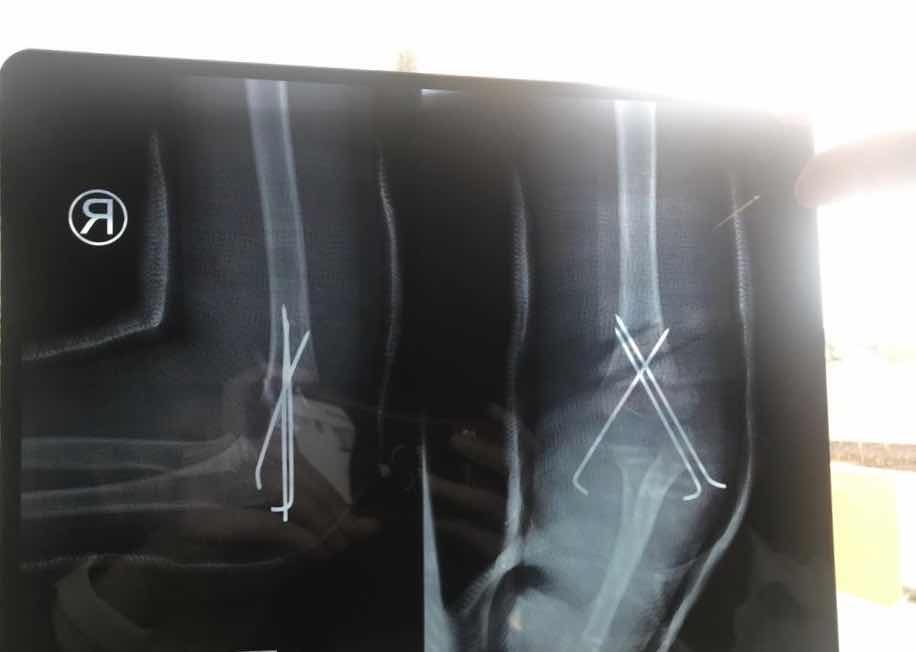

Now you can gasp. Not only is the bone now bones, the lower part is also twisted which could not be seen here.

Just out of surgery, little groggy. The little man had 3 wires inside him now.

So the doctor now said that he hasn’t seen such a serious case in 3 years and it’s the first time he put 3 wires instead of 2. I’m glad he didn’t say these before the surgery.

Bones in the right place now. Doctor said it could be better. But I’m already impressed that he moved them back in place without opening him up at all.